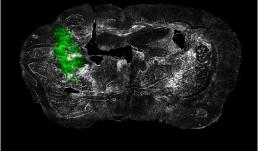

"Ex vivo coronal section of glioma cells, labeled with GFP (green), in a mouse model of glioblastoma (GBM) on day 14 of tumor development."

Image taken on Axioscan.

Author: Urbi Saha - Andrew Smith's Lab